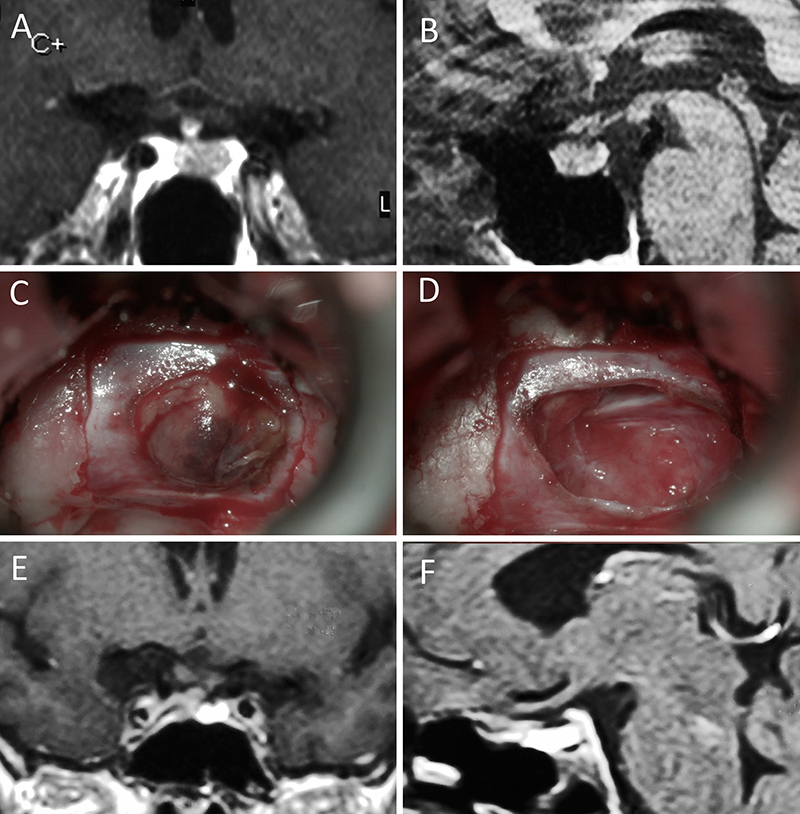

Figura 1: Macroadenoma no funcionante en mujer de 65 año s. Se decidió la cirugía tras evidenciarse crecimiento en los controles. Evolucionó favorablemente desde el punto de vista clínico-radiológico. A-B: RM preoperatoria; C-D: intraoperatorio; E-F: RM postoperatoria.

Figura 2: Macroadenoma no funcionante en mujer de 31 años. La paciente presentó en el preoperatorio déficit visual que mejoró tras la cirugía. A-B: RM preoperatoria; C-D: intraoperatorio; E-F: RM postoperatoria.